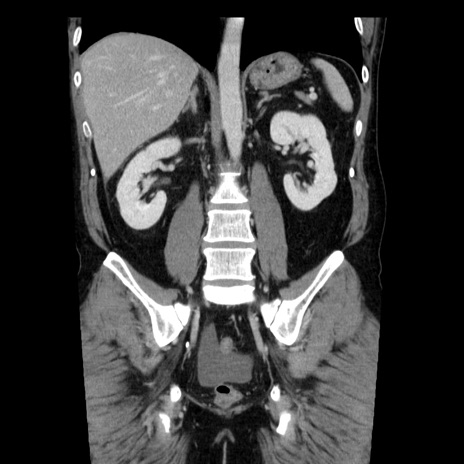

症例29(冠状断像)

【症例】40歳代男性

【現病歴】2日前から胃痛あり。徐々に周期的な激痛に変化した。本日になっても激痛があるため受診。

【身体所見】意識清明、BT 38-39℃台あり、腹部:膨満、やや硬、右下腹部に圧痛あり。

【データ】WBC 8500、CRP 23.26